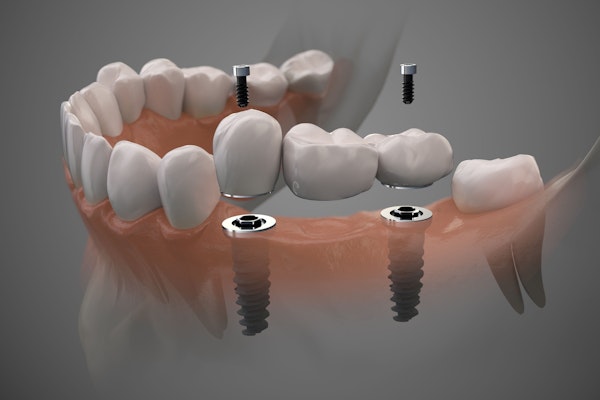

Dental Implant-Supported Bridges

Patients who opt for an implant-supported bridge will have a longer treatment timeline. First, the implants must be surgically placed into the jaw. Following this surgical procedure, three to six months of healing are required before the restoration can be placed. This gives the dental implants time to integrate with the surrounding bone tissue. Implants can also be used to secure dentures in place. This treatment option offers many benefits, including improved stability and oral function.